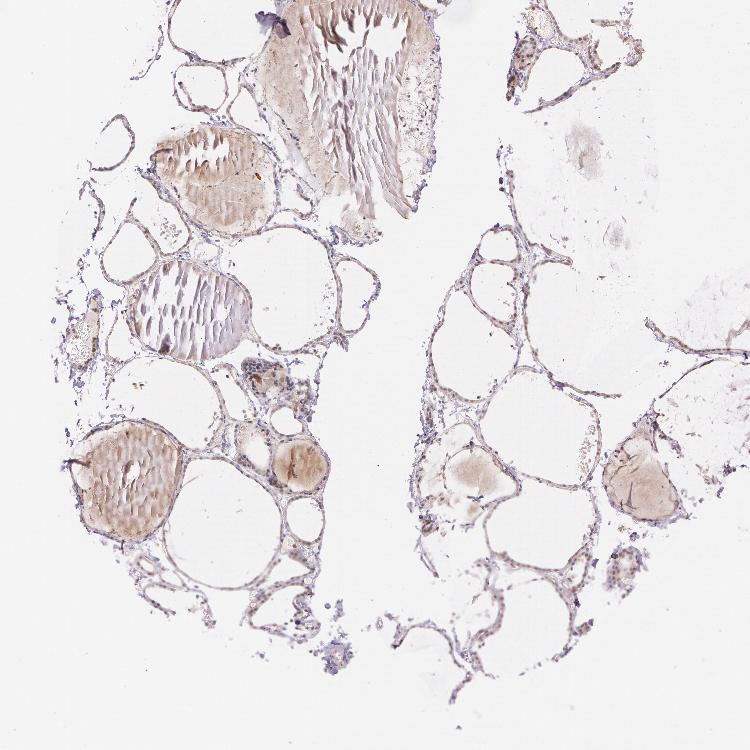

TISSUE PRIMARY DATA THYROID GLAND Show tissue menu

THYROID GLAND - Antibody stainingi

Antibody staining in the annotated cell types in the current human tissue is reported as not detected, low, medium, or high, based on conventional immunohistochemistry profiling in selected tissues. This score is based on the combination of the staining intensity and fraction of stained cells.

Each image is clickable and will lead to virtual microscopy that enables deeper exploration of all samples and also displays staining intensity scores, fraction scores and subcellular localization as well as patient and tissue information for each sample.

Antibody HPA001427Antibody HPA019665

Glandular cells LowNot detected